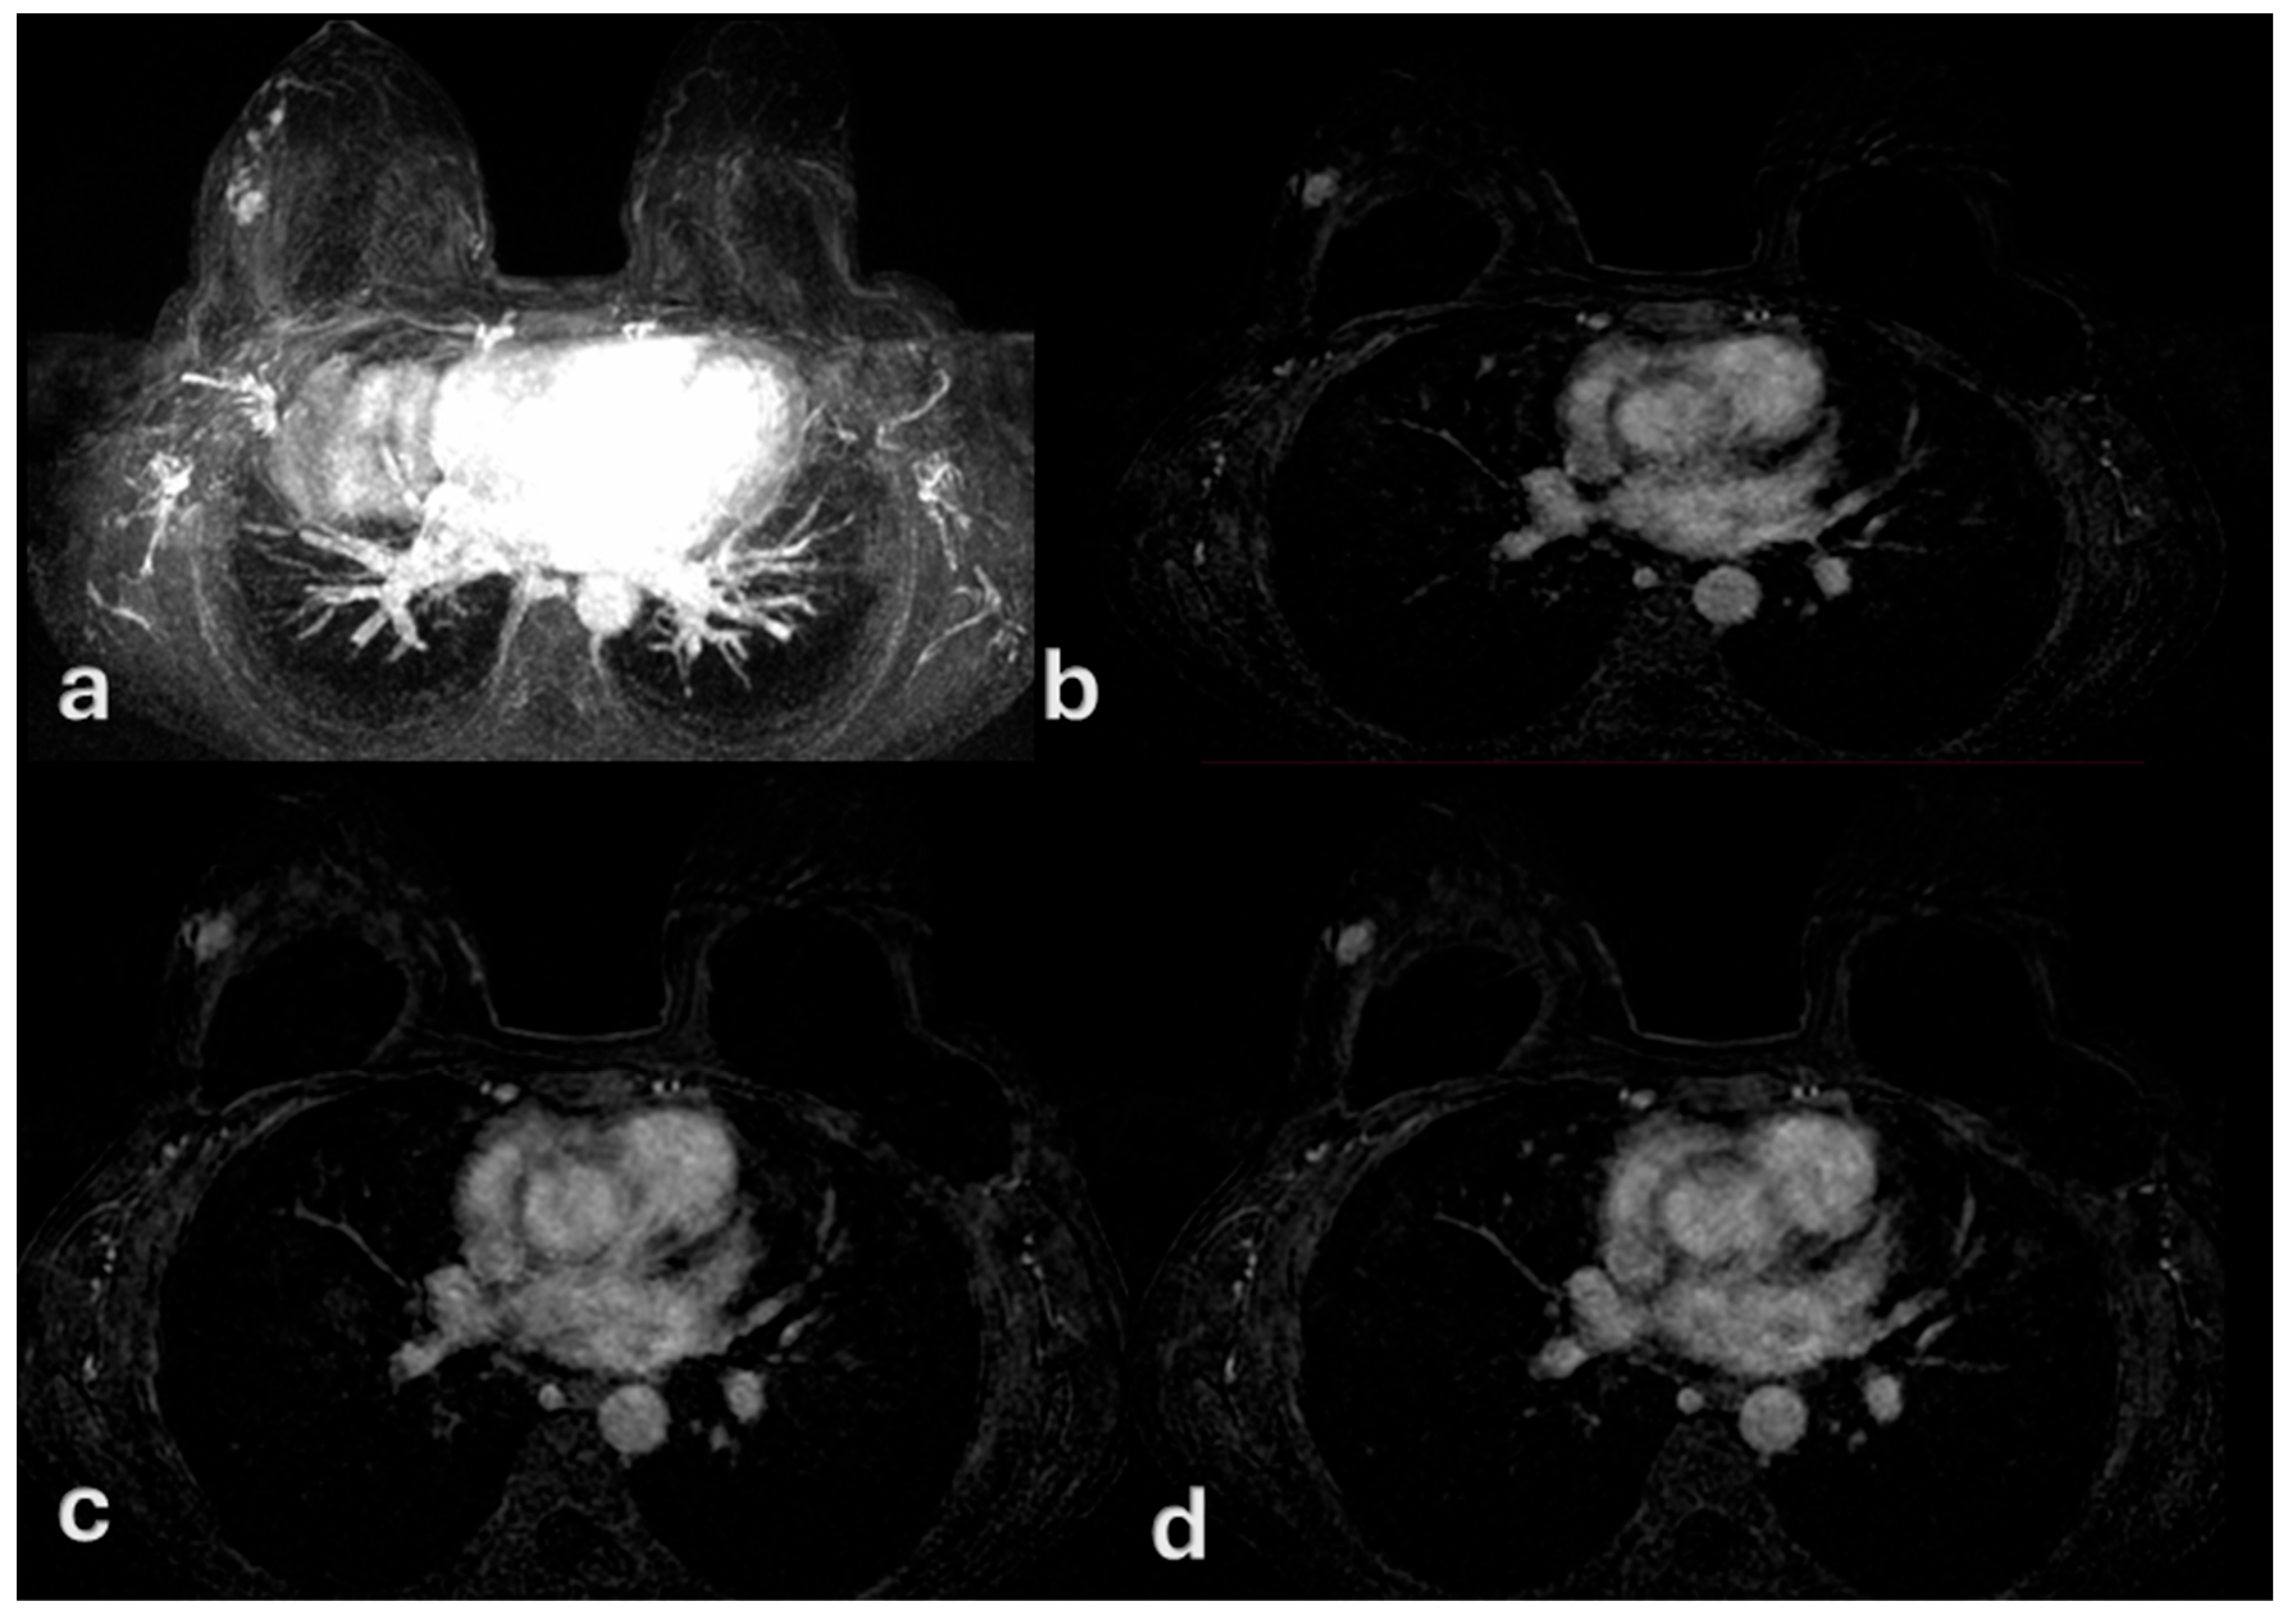

Multimodal Imaging of Ductal Carcinoma In Situ: A Single-Center Study of 75 Cases

3. Results